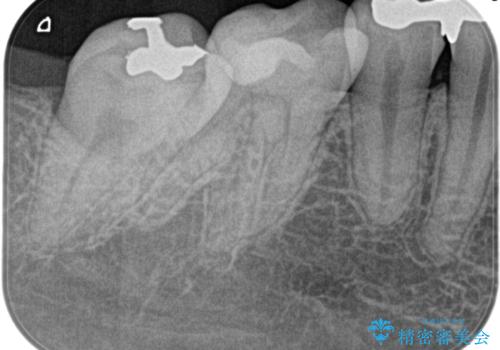

【根管治療】昨日から眠れないぐらい歯が痛い

- 昨日から夜も眠れないぐらい痛いことを主訴に来院されました。

検査の結果、不可逆性歯髄炎の診断とし根管治療を行なっております。

- 精密根管治療(イニシャルケース,大臼歯):122,000円、ファイバーコア:22,000円費用は治療当時の料金となります